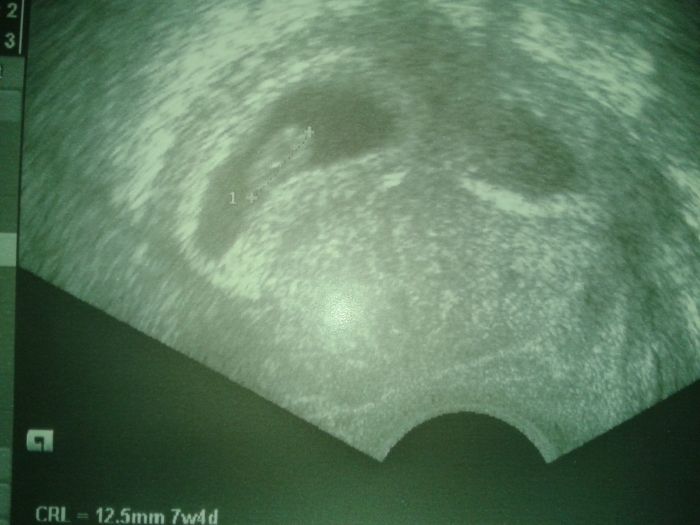

Holky tak vam povim zase dalsi zazitek... Vecer jsem začla krvacet ale jakoze hnedě a dost silně jenze sem si rikala ze jako do nemocnice nepojedu vecer by me nic stejne nedelali a muzu zajet rano, protoze spat muzu ve sve posteli. (zkusenosti z minule) no tak sem rano chtela na svou gyndu jenze ma dovču tak smůla tak sem musela do nemocnice. Tam byla uplne jina doktorka nez ty co tam byli minule tak jsem se dozvedela zase ze jsme o 3dni min :D takze uz to dela od menstruace nejakej tyden celej... Je to srandovni jak nejsou schopni se domluvit no.. Jinak samozrejme krvaceni hnedy byl ten hematom tak se trosicku zmensil ale furt me tam trapi dal :-( Ale konecne mam fotku tak se muzete podivat :-) mela jsem byt podle minule kontroly v nemocnici dneska uz 8+0 a jsem teda 7+4 no.... by me zajimalo jak tohle dopadne...snad dobre. jinak nemam tam dva ty cerny gestacni vacky to vpravo je prave ten hematom... tak uvidime snad to bude vse dobry.